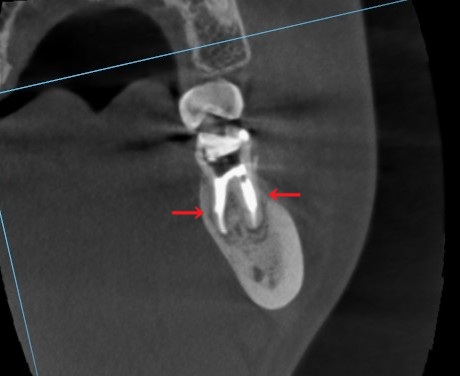

先ほどのCT写真で2つの根を1つずつ見ます。

まずはこちら、近心の歯根のを点線の断面で見てみます。

正面から見た歯の断面です。

青い矢印が長く根管に充填されていますが、歯の根には黒い影があります。

赤い矢印は根の横側へ、誤った方向に穿孔しています。

※穿孔(読み:せんこう)(英名:パーフォレーション)といって、本来の根管と違う方向に器具が進み、根管内に穴があいてしまっています。

間違った方向に歯を削り進めたため起こる医療ミスです。